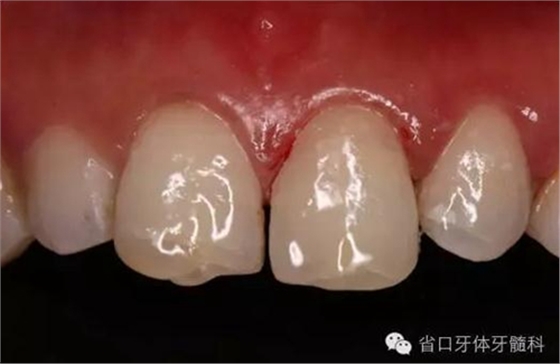

圖16. 術(shù)后口內(nèi)照

圖18. 術(shù)后23天隨訪的口內(nèi)照片